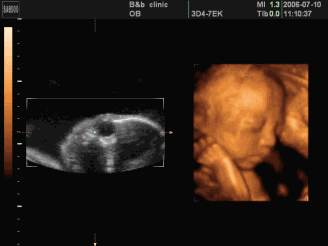

李想丽,女,超声诊断医师,具有执业医师和CDFI医师资格,在某地方医院从事超声工作10余年。曾在兰州大学第一附属医院超声科进修学习。擅长四维超声胎儿畸形筛查、腹部脏器、浅表脏器、妇产科彩超检查。

为了能更准确的检查胎儿是否健康,善懿堂诊所引进了我县首台高端四维彩超,不仅能检查胎儿是否健康,还能为胎儿拍宫内写真,受到了不少准爸妈的青睐。

四维彩超的检查时间有着很大的学问,只有在最佳时间里检查才能获得比较全面的检查效果,一般认为孕20周至28周是四维彩超检查的最佳时间。因为这个时段胎儿的肢体及各主要脏器已经全部发育,而且羊水较适合做胎儿畸形筛查。

1、全方位、多角度观察:四维彩超可以全方位、多角度地了解胎儿在宫内的生长发育状况,能够在早期诊断胎儿先天性身体表面畸形和先天性心脏疾病提供正确的科学依据。

3、胎儿体表检查:四维彩超还可以对胎儿的身体表面进行全面的检查,如唇裂,脊柱裂,脑积水,无脑儿,小头畸形,肾积水、心脏先天畸形、骨骼发育不健全等,提供了准确的科学的依据,并能及早的治疗。

4、实时动态活动图像:可以清楚的展示胎儿在宫内的实时动态活动图像。还可以将宝宝的样子以及动作制作成照片或动态视频,那么就可以让宝宝拥有最完整的0岁相册。